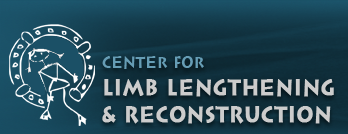

| This 54 year old lady, smoker, had a slip and fell on her hip. There was a fracture of the neck of femur on the left side. The options in such a situation are to either fix the fracture or replace the joint either half (Hemiarthroplasty-only the ball of the joint is replaced) or complete (Total Hip Replacement-boththe ball & socket are replaced). |

Since the hip joint was normal before the fracture, it was decided (with patient’s consultation) to do a fixation and try and salvage the hip. A closed reduction and percutaneus cancellous screw fixation (minimally invasive) was done. |

2 months post surgery |

The fracture seemed to be well on its way to heal. She was walking well though still with the walker. |